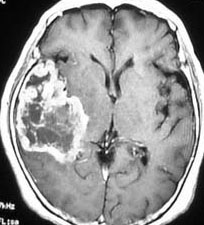

右側頭葉島の病変です。1年間の経過ではっきり増大したので,無症状でしたが生検術を行いました。病理組織では,異型グリアの増殖はありましたが,核分裂蔵,血管内皮の増生や壊死は明らかではありませんでした。しかし,遺伝子診断ではIDH1/2 野生型,ATRX retained,TERT promotor野生型,1p/19q共欠失なしでした。膠芽腫という確定病理診断です。

標準治療を加えましたが,数ヶ月後に急激な増大を呈しました。グレード4の臨床像です。MRI画像よりも病理組織像よりも,遺伝子診断の方がより性格に予後を示す例です。